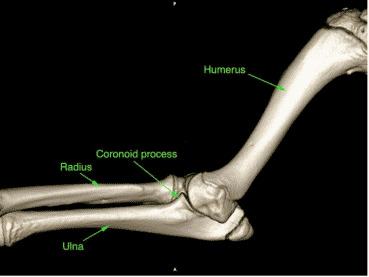

The elbow is the joint formed by the humerus, radius and ulna. Dysplasia results when the bones do not match each other well (known as incongruency). There are various abnormalities but the result of these is overloading at parts of the joint. The most common problem is fragmentation of the medial coronoid process. This lip of bone on the ulna can become detached resulting in a fragment of bone and cartilage, leading to pain in the joint.

Conditions like fragmented coronoid process usually require CT imaging for accurate diagnosis. CT uses X-rays like traditional radiographs but can provide much more detail and allow a 3D image to be constructed. The detail is required because the area may be small (sometimes only a crack running across the area). We can also assess the incongruency (how well the joint fits together) to some extent.